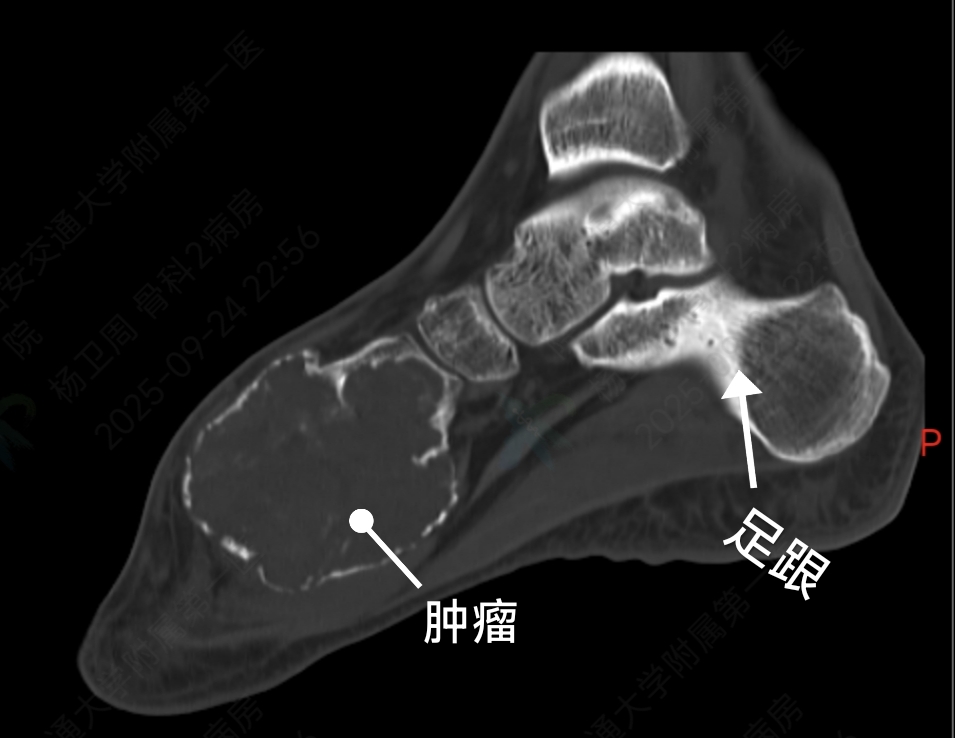

术前影像检查显示,肿瘤已严重破坏其内侧楔骨及第一跖骨,并形成一个被薄层骨壳包裹的巨大软组织肿块。治疗面临两难选择:若彻底切除肿瘤,将造成第一跖骨缺损,影响行走功能;而若仅行刮除术,则复发风险显著增加。面对这一复杂病例,韩学哲与边卫国教授迅速启动多学科协作机制,联合整形外科何林教授团队深入研讨,最终制定了“第一跖骨及内侧楔骨切除+带血管蒂腓骨移植重建”的手术方案。